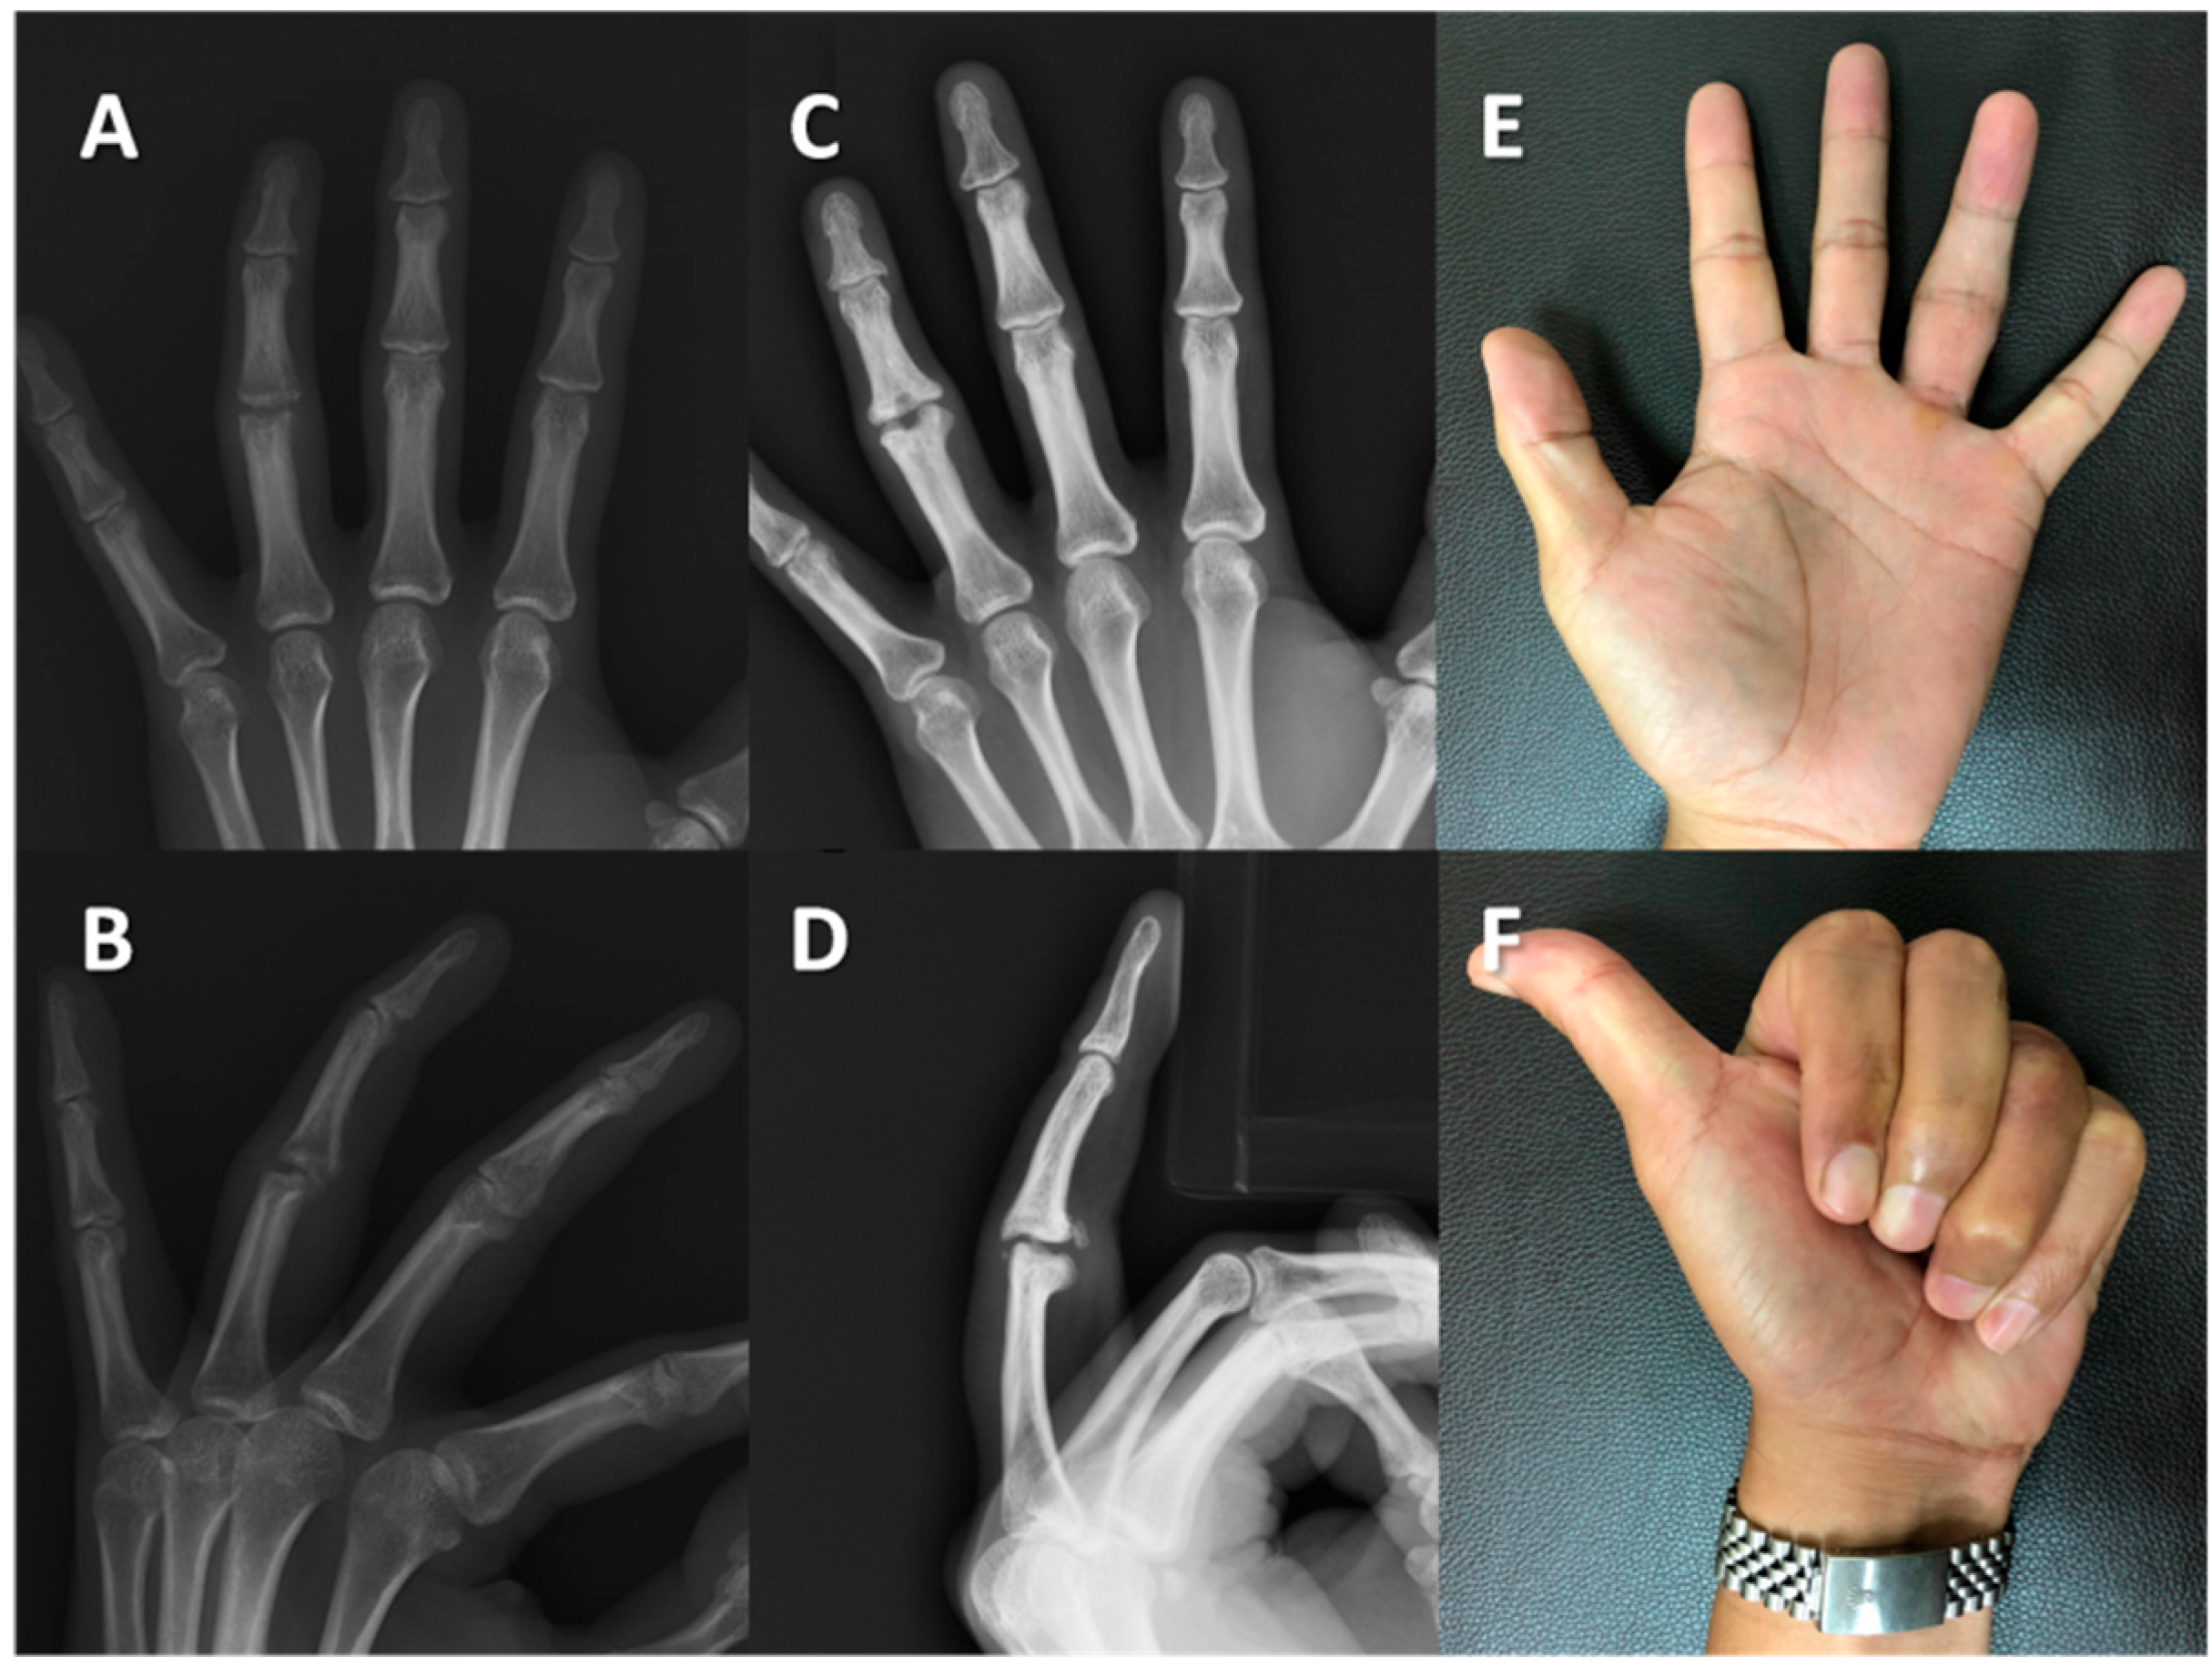

Figure 4. Case #8: A 57-year-old woman developed left middle finger post-traumatic osteoarthritis. Radiographs of the left middle finger in the (A) anteroposterior (AP) view and (B) lateral view revealed post-traumatic osteoarthritis of the proximal interphalangeal joint in the preoperative status. The five-year follow-up assessment demonstrated the preservation of joint space in the (C) AP and (D) lateral views. The active flexion of the finger was 40° (E) with no extensor lag (F).